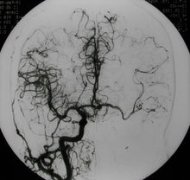

颈动脉海绵窦瘘(carotid-cavernous fistula,CCF)一般指颈内动脉海绵窦段的动脉壁或其分支发生破裂,以致与海绵窦之间形成异常的动静脉交通。由颈内动脉和(或)颈外动脉的硬脑膜支血管与海绵窦形成侧异常交通称为海绵窦硬膜动静脉瘘。 颈动脉海绵窦瘘...[详细]

颈动脉海绵窦瘘是指海绵窦段的颈内动脉本身或其在海绵窦内的分支破裂,与海绵窦之间形成异常的动静脉沟通,少数颈动脉海绵窦瘘由颈外动脉供血,特称颈外动脉海绵窦瘘。75%以上的为外伤引起,称为外伤性CCF,其余无外伤史者,称为自发性海绵窦瘘。最常见...[详细]

颈动脉海绵窦瘘(carotid-cavernous fistula,CCF)一般指颈内动脉海绵窦段的动脉壁或其分支发生破裂,以致与海绵窦之间形成异常的动静脉交通。由颈内动脉和(或)颈外动脉的硬脑膜支血管与海绵窦形成侧异常交通称为海绵窦硬膜动静脉瘘。 (一)发病原因...[详细]